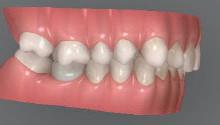

Dental Tribune Bulgarian Edition / октомври 2022 г.16 клиничен случай с алайнери Г орният латерален ре зец е вторият найчесто вродено липсващ зъб.1,2 Поради разполо жението му във видимата зона на усмивката лечение то на подобни случаи нала га мултидисциплинарен под ход, целящ отличен функцио нален и естетичен резултат. Налице са няколко лечебни мо далности, свързани с различ но разпределение на място то: първият вариант е орто донтско отваряне на място и възстановяване на липсва щия зъб с конструкция, под държана от съседните зъби3 или от имплант4, докато при втория подход разстоянията се затварят и премоларът заема мястото на канина.5 Изборът на лечебен подход трябва да бъде направен съв местно от зъболекар и паци ент въз основа на очакванията на последния и предвиди мостта на лечението. Множе ство фактори влияят върху това решение, като напри мер типа малоклузия, размера, формата и цвета на кучеш ките зъби6, оклузалните вза имоотношения (овърджет и овърбайт), лицевия профил, дължината на зъбната дъга и несъответствията в разме ра на зъбите.7 В настоящата публикация се разглежда случаят на жена в зряла възраст с вродена лип са на горен ляв латерален резец. Бяха приложени про зрачни алайнери за отваряне на място за единичен им плант и бяха постигна ти функционална оклузия и отлична естетика. ПРЕДСТАВЯНЕ НА СЛУЧАЯ Диагноза Пациентката бе на 32 годи ни, когато лечението започна, и първоначалното ѝ състоя ние бе следното (фиг. 1–3): липсващ горен ляв латерален резец; клас II, подклас I малоклузия; отклонение на горната сре динна линия вляво; Доклад на клиничен случай ЛЕЧЕНИЕ С АЛАЙНЕРИ НА ПАЦИЕНТ С АГЕНЕЗИЯ НА ЛАТЕРАЛЕН РЕЗЕЦ Д-р Iro Eleftheriadi и д-р Christodoulos Laspos, Гърция и Кипър Фиг. 1a–h Предоперативни лицеви и интраорални снимки. Фиг. 2a–e Дигитални модели преди началото на лечението. Фиг. 3 Панорамна снимка преди лечението. Фиг. 1a Фиг. 1d Фиг. 1f Фиг. 2a Фиг. 2d Фиг. 2b Фиг. 2e Фиг. 3 Фиг. 2c Фиг. 1b Фиг. 1e Фиг. 1g Фиг. 1h Фиг. 1c

Dental Tribune Bulgarian Edition / октомври 2022 г. 17клиничен случай с алайнери леко струпване в долната че люст; несъответствие по Болтън (мандибуларен излишък от 3.06 мм във фронталната зона и общо 1.47 мм); издължено лице с лицева аси метрия; конвексен профил с ретруди рана долна челюст и проми нентен нос. На мястото на зъб #46 бе на лице имплант, а зъби #16 и 26 са ендодонтски лекувани. Тези зъби бяха асимптоматич ни, затова бе взето решение да се прави релечение само при нужда. Мъдреците липсваха. Анализът на телерентгеногра фията (фиг. 4) показа ретрог натна мандибула (SNB: 74.2°) и нормална инклинация на резците както в

Цели на лечението и лечебен план Целите на лечението бяха следните: нивелиране и подреждане на зъбите и в двете зъбни дъги; отваряне на пространство за липсващия латерален резец; коригиране на отношенията при канините и моларите до клас I; и корекция на отклонението на срединната линия. Лечебният план включваше: корекция на отношенията при кучешките зъби и мола рите до клас I с дистализира не на максилата; отваряне на пространство в областта на #22 за поставя не на единичен имплант; корекция на срединната ли ния; и създаване на място за раз ширяване на зъб #12 и апрок симална редукция в долната челюст с цел подобряване на несъответствието по Болтън и осигуряване на подобра оклузия. Изпълнение на лечебния план Този случай бе изпълнен със системата за алайнери Invisalign (Align Technology). Одобреният първоначален лечебен план предвиждаше 49 алайне ра с дистализиране на задни те горни зъби до клас I (прибли зително с около 3.5 мм; фиг. 5). За бъдещия имплант в областта на липсващия латерал бе планирано пространство от 6.5 мм, докато във фронталния сегмент на долната челюст бе предвидена апроксимална редук ция. В дясната страна бутон за ластици клас II бе поставен на зъб #47 вместо на зъб #46, за да не се увреди короната на импланта. Понеже пациентката жи вееше в чужбина,